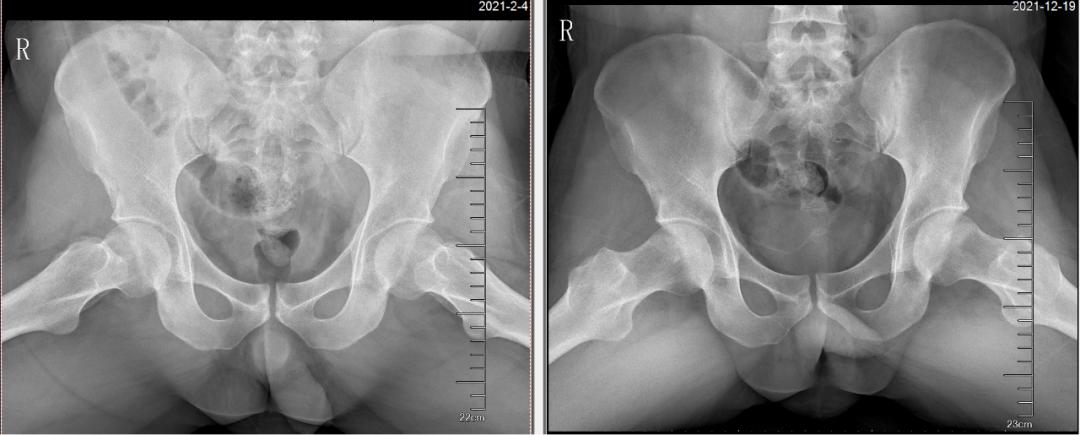

“来到广州以后,通过预约挂号,来到何伟教授的股骨头坏死专家门诊,何伟教授详细询问了我的病史、作详细体格检查,安排双髋关节正、蛙位X片与磁共振检查,并仔细询问我的家庭情况、教育背景、工作规划后,告诉我 由于长期、大量使用糖皮质激素,导致双侧股骨头坏死 ,其中右侧坏死范围较大,有一定的塌陷风险,遂建议我入院进行系统非手术保髋治疗。”听到何教授的建议,小王跟母亲商量后决定治疗,抱着试试看的心理,他接受了大概两周的综合治疗,包括中药内服、外用、严格拄拐行走、冲击波、个体化的运动治疗。

“我看过很多医生,你们的非手术保髋真的有效果吗?”这是小王在住院期间常对康复治疗师和医生说的话。没想到住院快要结束时,小王的疼痛就缓解了不少,这让小王惊喜不已,他开始认可三院非手术保髋的疗法。出院后小王又按照何伟教授的要求,认真拄双拐、坚持服药,三月后复查的磁共振、X光显示病情比较稳定,他便预约第二次入院治疗,经过半年时间的治疗,现在小王已经基本恢复了正常生活。

△治疗前后X光片、磁共振对比可见:双侧股骨头坏死修复,未发生塌陷,病情稳定